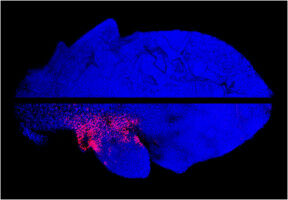

Neue Mikroskopiemethode macht Unterschiede zwischen Schädelund Röhrenknochen sichtbar Lebender Knochen fasziniert durch seine besondere Fähigkeit, sich mechanischen Belastungen anzupassen und ohne Narbenbildung zu regenerieren. Bei der Frakturheilung arbeiten Blutgefäße und Knochenzellen eng zusammen, wobei das zunächst aus Knorpel gebildete Wundgewebe allmählich durch einwachsende Blutgefäße und neues Knochengewebe ersetzt wird.